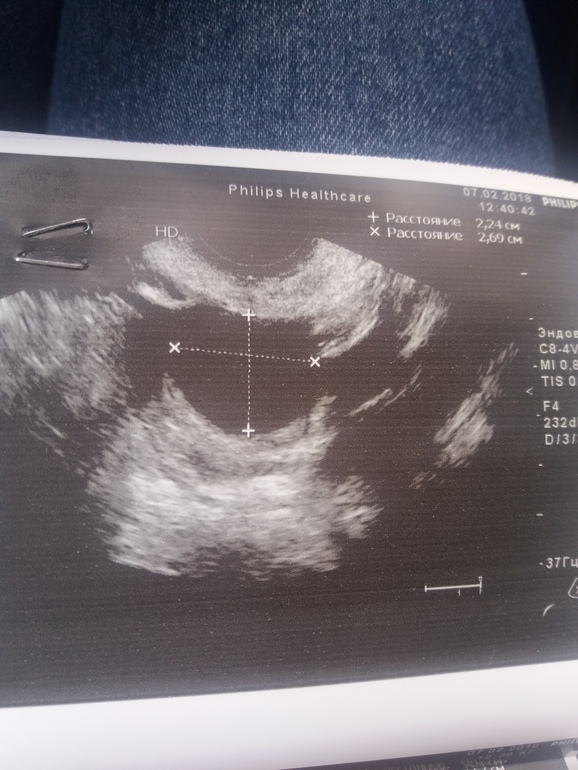

Что это за результат узи ?

спросила про неоднородность. врач сказала, что О ранняя была и эндрик в процессе роста она мне экране показала , поэтому не успел стать однородным, но он успеет принять нужный вид до имплантации. )))) как то так врач обьяснила. ЖТ огромное, и не понимаю почему его кистой назвали, в прошлом цикле жт 15 было

Могли назвать кистозным желтым телом, но по фото кажется, что действительно киста ЖТ. Эндометрий не описывают все же как неоднородный, это всегда расценивается как отклонение от нормы, но хорошо, что врач объяснила.